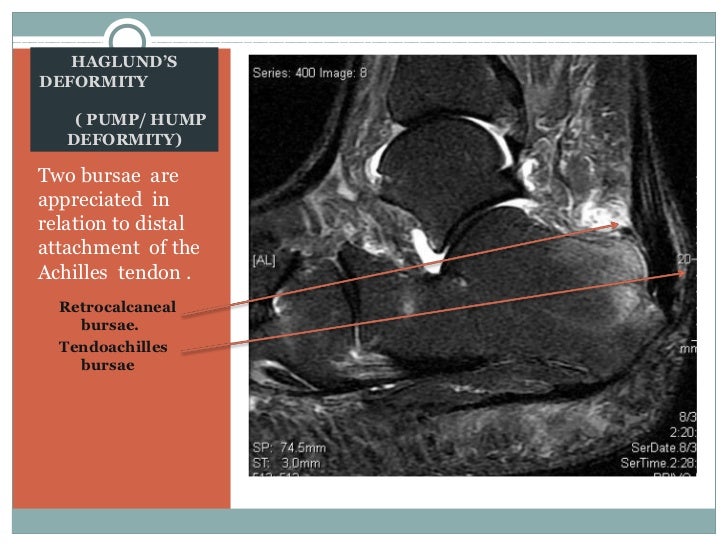

Haglund's syndrome is a group of signs and symptoms consisting of haglund's deformity (which is an exostosis of the posterior calcaneal tuberosity) in combination with retrocalcaneal bursitis. Haglund's deformity is characterized as an enlarged prominence of the superior aspect of the posterior calcaneus, which can cause painful inflammation within the retrocalcaneal bursa and anterior surface of the achilles tendon as a result of mechanical irritation. Other names for haglund's deformity include bauer bump, pump bump, or mulholland deformity, though it's most commonly known as haglund's heel. When this bony enlargement rubs against the achilles tendon and overlying bursa, inflammation of the retrocalcaneal bursa occurs. Haglund deformity radiology reference article. The presence of a haglund's deformity narrows this space considerbly thereby casuing or exacerbating problems such as retrocalcaneal bursitis. Haglund's deformity is a bony enlargement at the level of the posterior part of the heel. Haglund's deformity is a bony enlargement on the back of the heel. Haglund deformity, also known as a pump bump , bauer bump, or mulholland deformity, is defined as bony enlargement formed at the posterosuperior aspect of the calcaneum. The soft tissue near the achilles tendon becomes irritated when the bony enlargement rubs against shoes. Halgund's deformity is a condition in which a bony enlargement is formed in the heel. Over time the tissues also usually thicken over the bone bump, causing a callus to form. It is a small, often pointy haglund's deformity can cause pain at the back of the heel increasing during strain.

Haglund's syndrome is a group of signs and symptoms consisting of haglund's deformity (which is an exostosis of the posterior calcaneal tuberosity) in combination with retrocalcaneal bursitis.